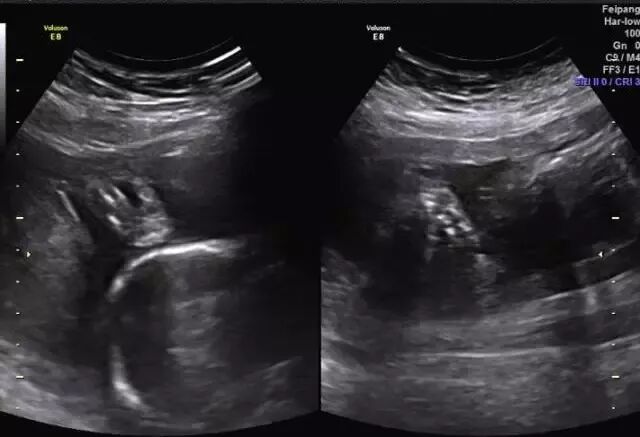

胎儿常见畸形检查图

(右侧缺指)

(左肾缺如)